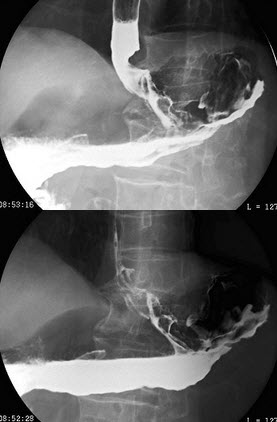

120、单项选择题

男,75岁,吞咽困难3月,伴胸痛,结合图像,最可能的诊断为()

A.贲门癌

B.胃底癌

C.食管下段癌

D.贲门癌侵及食管、胃底

E.食管胃底静脉曲张